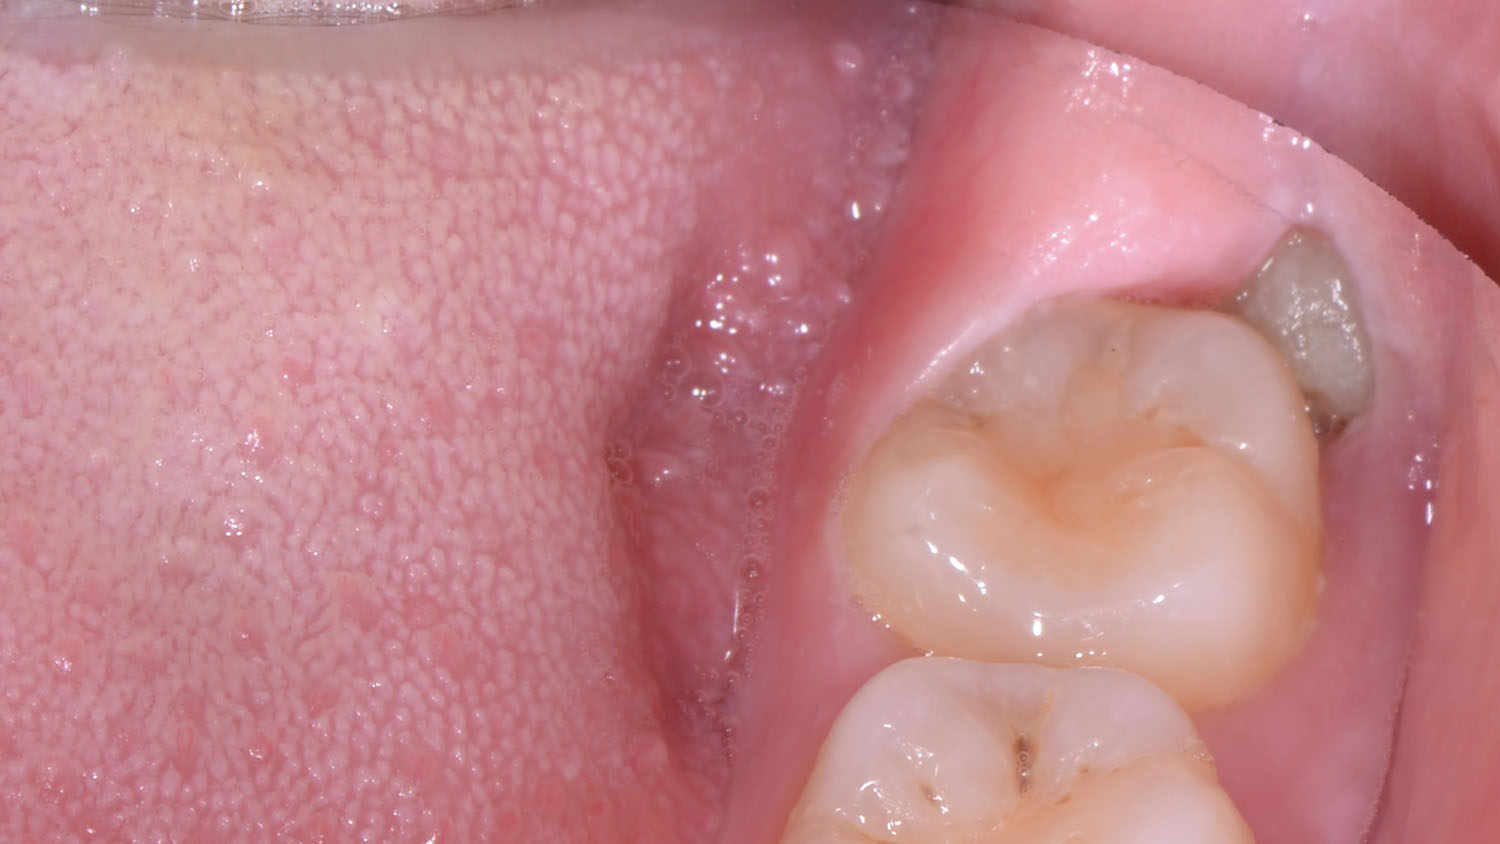

Sau khoảng 12 tuổi, răng khôn (nếu có) đã hình thành xong thân răng. Không thể xác định chính xác thời gian mọc của răng khôn, nó rất thay đổi trên từng cá thể, vào khoảng 17-21 tuổi. Nhìn chung ở nữ giới răng khôn thường mọc sớm hơn ở nam giới. Răng khôn là răng mọc muộn nhất trên cung hàm và thường không có đủ chỗ để mọc, nên thường mọc lệch, thậm chí ngầm hoàn toàn trong xương không mọc lên được. Răng khôn mọc lệch gây nhiều biến chứng như viêm nhiễm, rối loạn chức năng nhai, gây ra hoặc làm trầm trọng bệnh lý khớp thái dương hàm. Một số trường hợp răng khôn mọc tạo áp lực đẩy ra trước làm xô lệch nhóm răng cửa, đặc biệt là răng cửa hàm dưới.

Hình ảnh răng khôn mọc lệch, lợi trùm, có thể gây nhiều biến chứng nguy hiểm